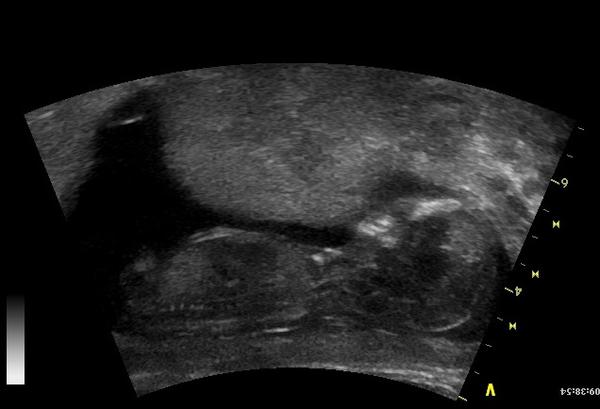

Holky co byste si tiply? Holčička nebo chlapeček? Necháváme si překvápko, ale zvědavá samozřejmě jsem ;)

@jajajajajaja my mame podobny obrazek a je z toho kluk 🙂 Otazka jestli je to to, co to ma byt, nebo pupecni snura 🙂